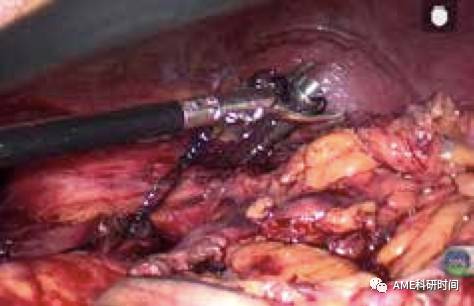

2侧方置入法:扩大左上腹腋前线主操作孔至2~2.5 cm,置入钉座。在食管预断离的平面远端用边带捆绑,打开食管前壁约1.5~2 cm(最好横行打开,如 图7-10),中心杆置入食管内,顶住对侧管壁并在相应位置戳一小孔,穿出中心杆,再将整个钉座带入食管内,用直线切割闭合器在第一次开口上方断离食管,注意尽量靠近中心杆(如图24)。

管型吻合器怎么用完全腹腔镜下全胃切除术后的消化道重建——7种食管空肠吻合方法_https://www.jmylbn.com_新闻资讯_第7张

图7 打开食管前壁

管型吻合器怎么用完全腹腔镜下全胃切除术后的消化道重建——7种食管空肠吻合方法_https://www.jmylbn.com_新闻资讯_第8张

图8 对侧壁穿出中心杆

管型吻合器怎么用完全腹腔镜下全胃切除术后的消化道重建——7种食管空肠吻合方法_https://www.jmylbn.com_新闻资讯_第9张

图9 牵拉出中心杆

管型吻合器怎么用完全腹腔镜下全胃切除术后的消化道重建——7种食管空肠吻合方法_https://www.jmylbn.com_新闻资讯_第10张

图10 置入钉座